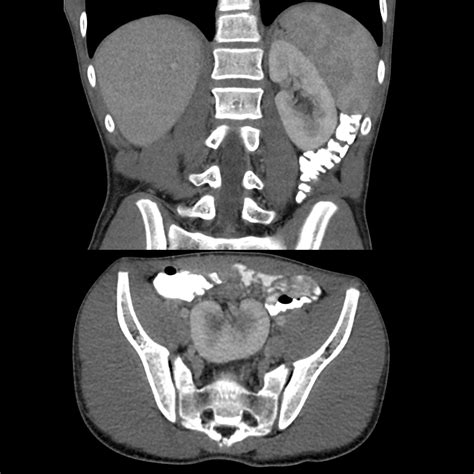

If your doctor suspects an ectopic kidney, they will use imaging technology to confirm the location and assess the health of the renal tissue. Early detection is vital for monitoring function. Common diagnostic methods include:

CT/MRI Scans Used for detailed cross-sectional views if further analysis is needed.

⚠️ Note: Always discuss the necessity of radiation-based tests (like CT scans) with your healthcare provider, especially in younger patients, to balance diagnostic benefits against radiation exposure.

• ectopic kidney ct

• ectopic kidney radiopaedia